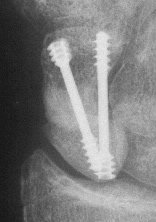

Case 7. This nonunion patient's scaphoid and iliac crest were unusually soft bone.

Click for larger image

After two screws, the fixation was clearly inadequate, so I put a third screw through the graft into the proximal pole. I wasn't sure whether to buy

stock in Herbert screws or Zantac. The fracture healed despite AWOL and no immobilization.